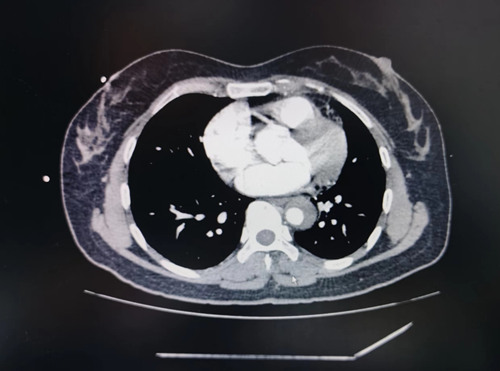

为了尽快明确诊断,绿色通道各部门快速联动,紧急进行急诊增强CT检查,检查结果示:主动脉改变,考虑主动脉夹层。夹层从主动脉弓撕裂到肾动脉,病情非常危急!明确诊断后,考虑到此病内科保守治疗效果差,需转运至具备体外循环、升主动脉置换条件的上一级医院进行治疗。随即,怀化市第五人民医院派出专科医生和护士将患者护送到上级医院进一步治疗。